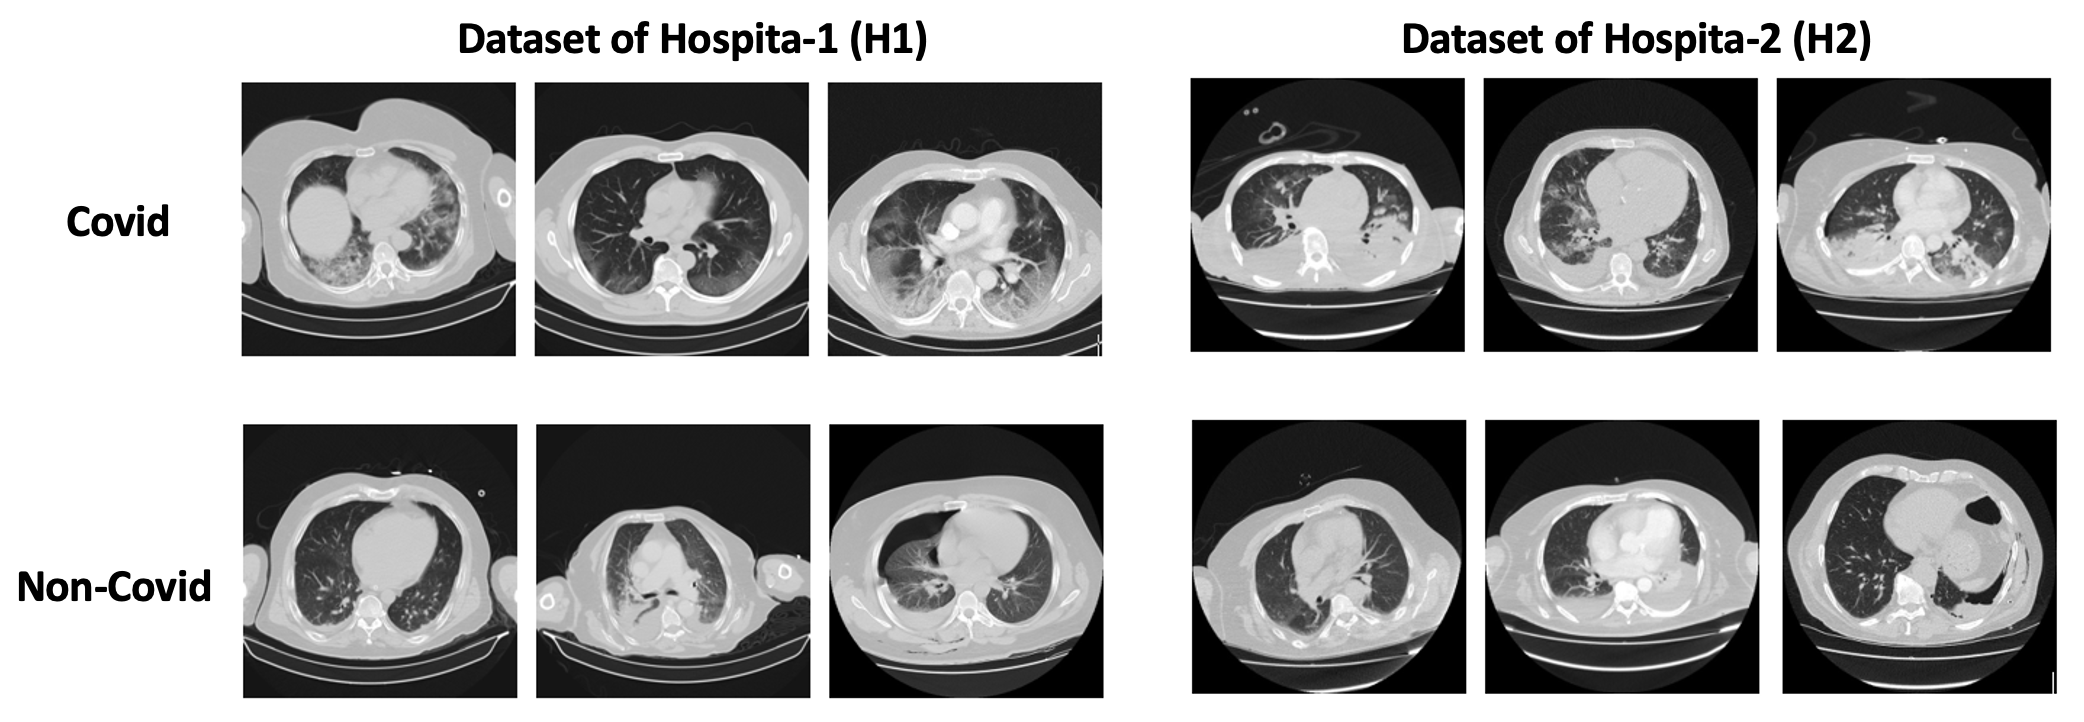

These datasets, H1 and H2, are more appropriate for our task because they provide an adequate number of samples in terms of both patients and slices, thus supplying the necessary information for our models. An indicative sample of these data is found in Figure-1. The number of the samples related to dataset H1 and H2 are presented on Tables-1 and 2 respectively.

Refer to caption

Figure 1: Samples of CT slices from our datasets.